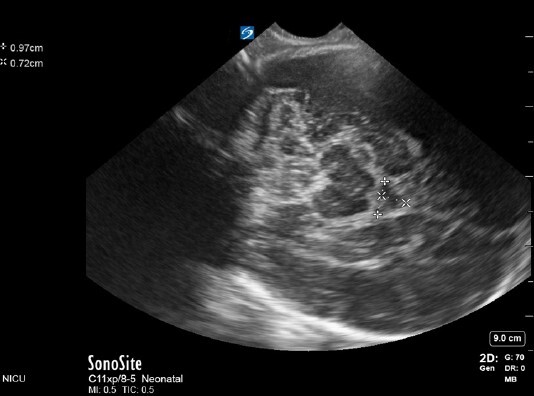

Neonatology 4th Ventricle Measurement Image